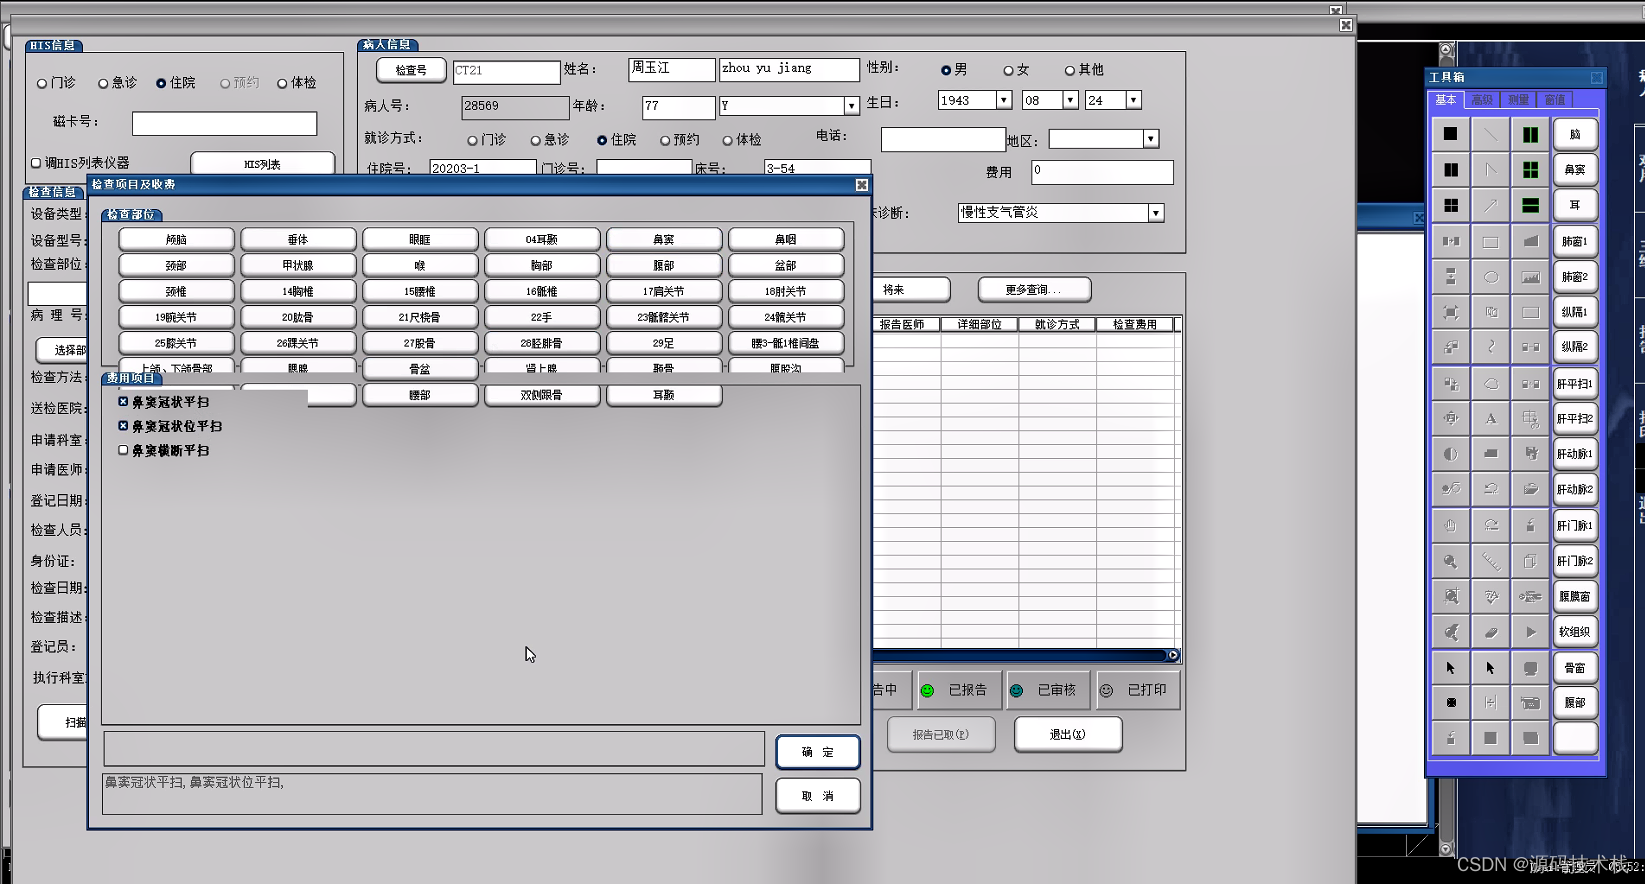

信息预约登记

支持对患者、检查项目、申请医生、申请单据、设备等信息进行管理。且支持检查病人排队管理功能;

支持大屏幕队列显示和语音呼叫;

提供预约调整、插队管理和掉队处理等功能;支持急诊申请优先安排。

报告管理

系统支持支持报告编写界面按检查项目分类显示患者列表;

提供 图文报告的书写、修改、审核功能,支持权限管理;

1. 临床医生在医生工作站中录入电子检查申请单,并将申请单传入RIS系统。

2. 影像检查科室的RIS中对电子检查申请单的信息进行预约、审核、划价确认。